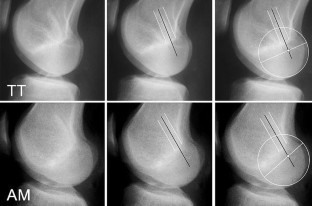

Correct placement of the tibial and femoral bone tunnel is prerequisite to a successful anterior cruciate ligament (ACL) reconstruction. This study compares the resulting radiographic femoral bone tunnel position of two commonly used techniques for arthroscopically assisted drilling of the femoral bone tunnel: the transtibial approach or drilling through the anteromedial arthroscopy portal. The resulting bone tunnel position was assessed in postoperative knee radiographs of 70 patients after ACL reconstruction. Three independent observers identified the femoral bone tunnel and determined its position in the lateral and A–P view. Differences in femoral tunnel position between transtibial and anteromedial drilling were evaluated. In the sagittal plane, significantly more femoral bone tunnels were positioned close to the reference value using an anteromedial drilling technique (86%) when compared to transtibial drilling (57%). Drilling through the transtibial tunnel resulted in a significantly more anterior position of the femoral tunnel. In the frontal plane, femoral bone tunnels which were placed through the anteromedial arthroscopy portal displayed a significantly greater angulation towards the lateral condylar cortex (50.92°) when compared to transtibial drilling (58.82°). In conclusion, drilling the femoral tunnel through the anteromedial arthroscopy portal results in a radiographic femoral bone tunnel position which is suggested to allow stabilization of both anterior tibial translation and rotational instability when using a single bundle reconstruction technique. Further studies may evaluate if there are any clinical advantages using the anteromedial portal technique.

Fig. 3